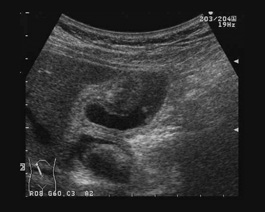

急性胆嚢炎はどのように診断されますか?

急性胆嚢炎の症状は他の多くの病気に似ている場合があります。医師は症状だけでなく病歴についても知りたいと考えます。おそらく腹部に腫れや圧痛のある部分がないか検査されるでしょう。次のような追加の検査を注文する場合があります。